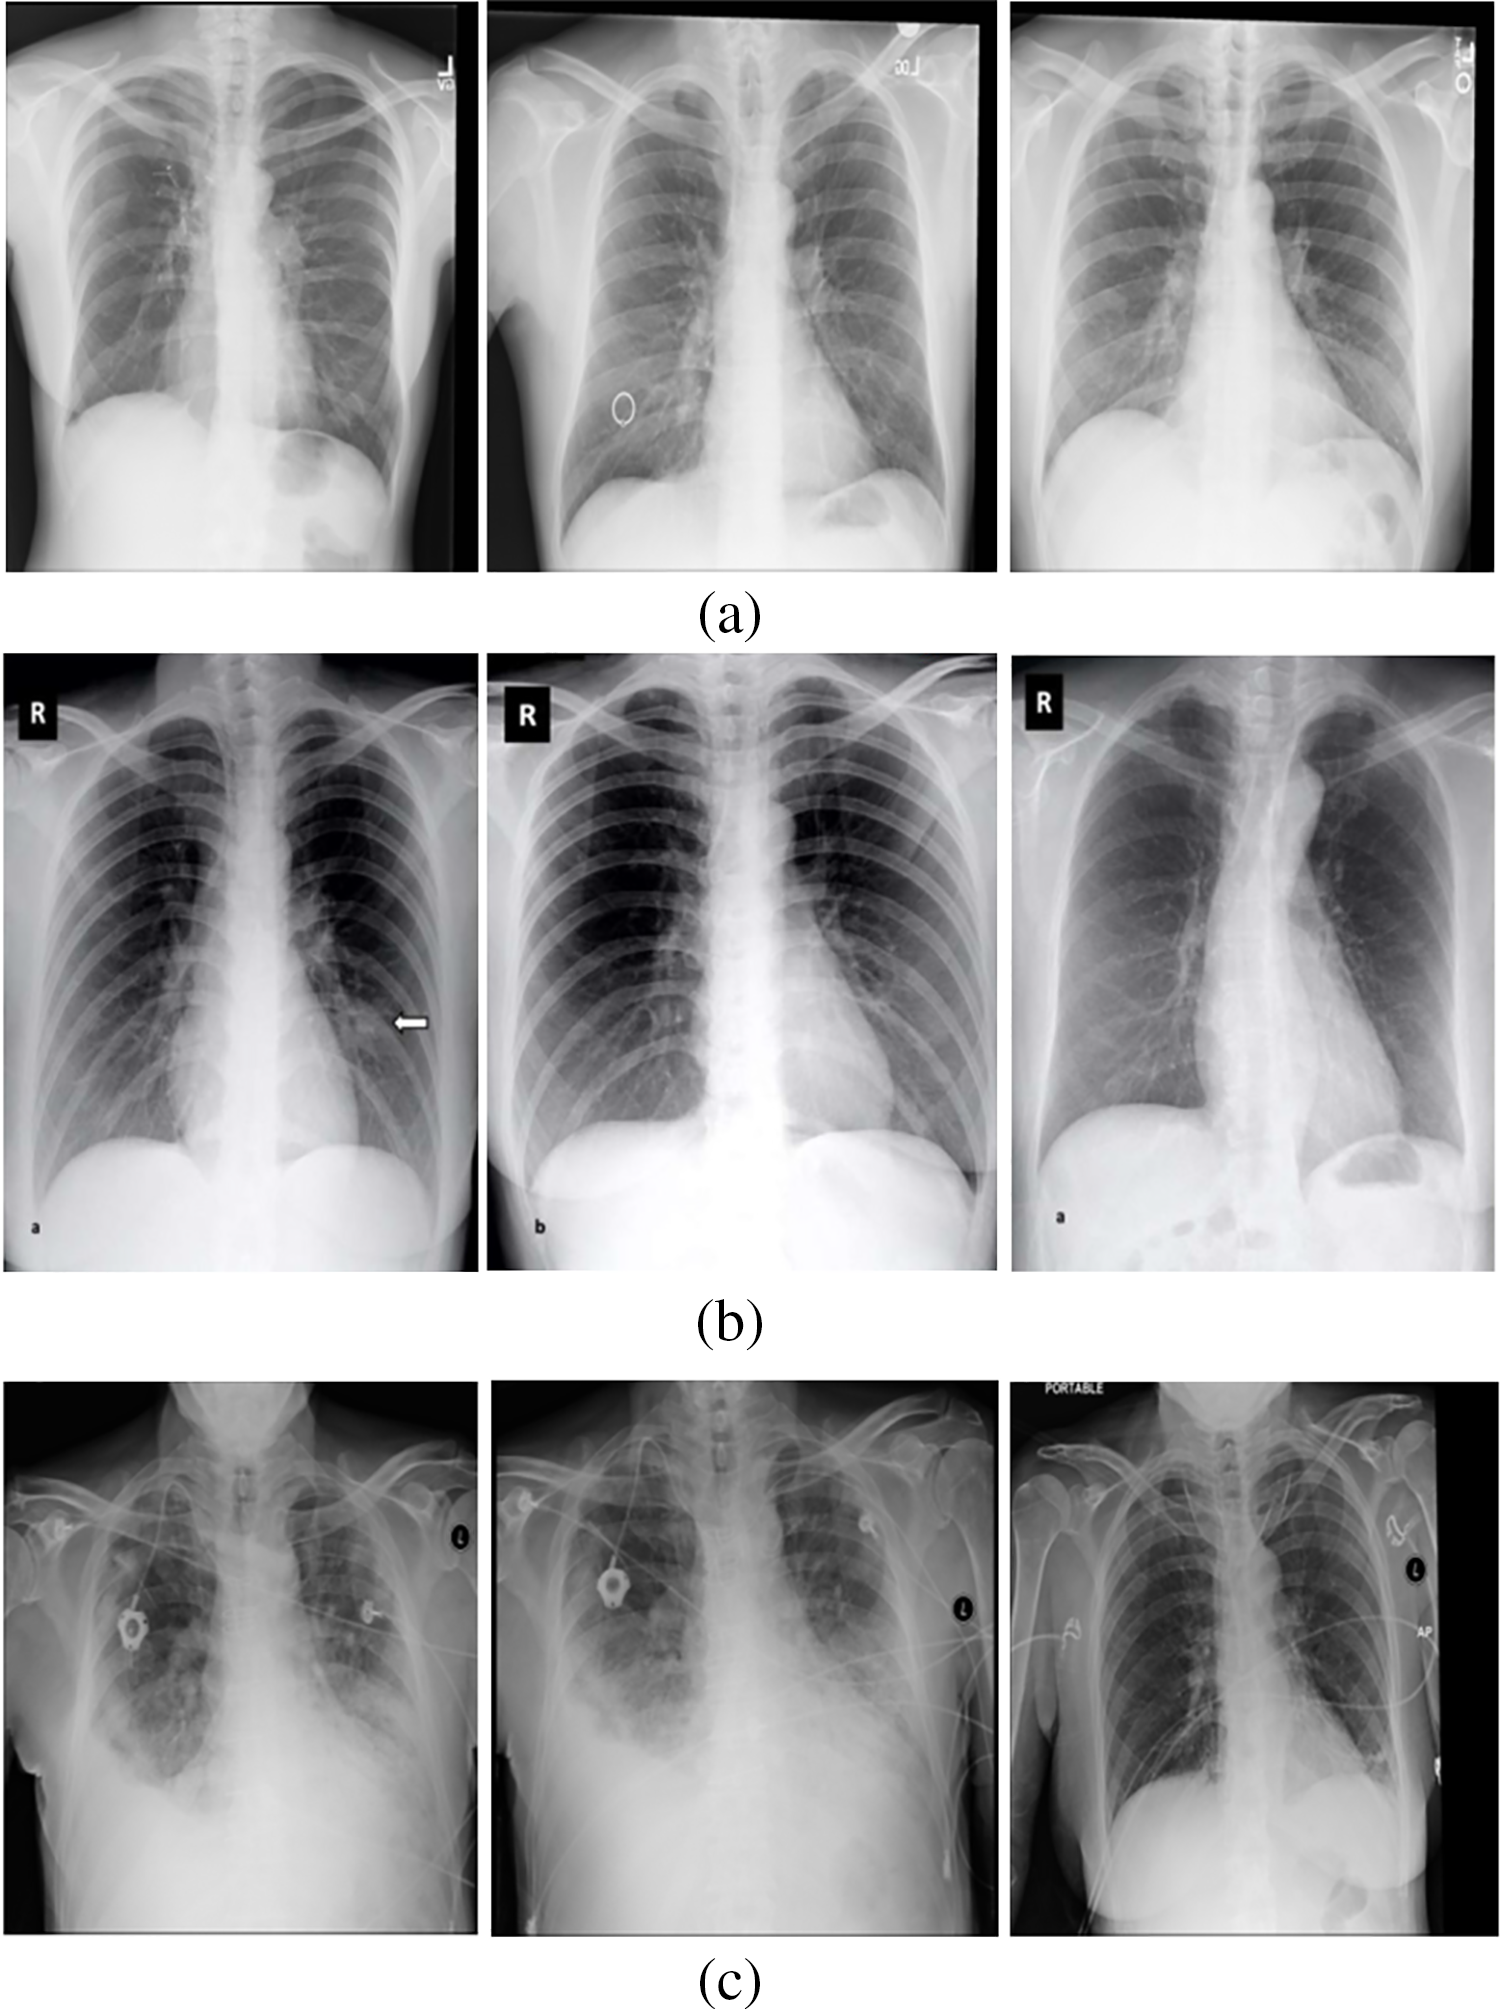

Around 234 normal, 390 Pneumonia, and 267 COVID-19 X-ray images are considered as input. Fig. 6 contains the images of various categories. The preprocessing results of the MADF technique are demonstrated in Fig. 7.

Figure 6: (a) Normal category (b) COVID-19 category (c) Pneumonia category